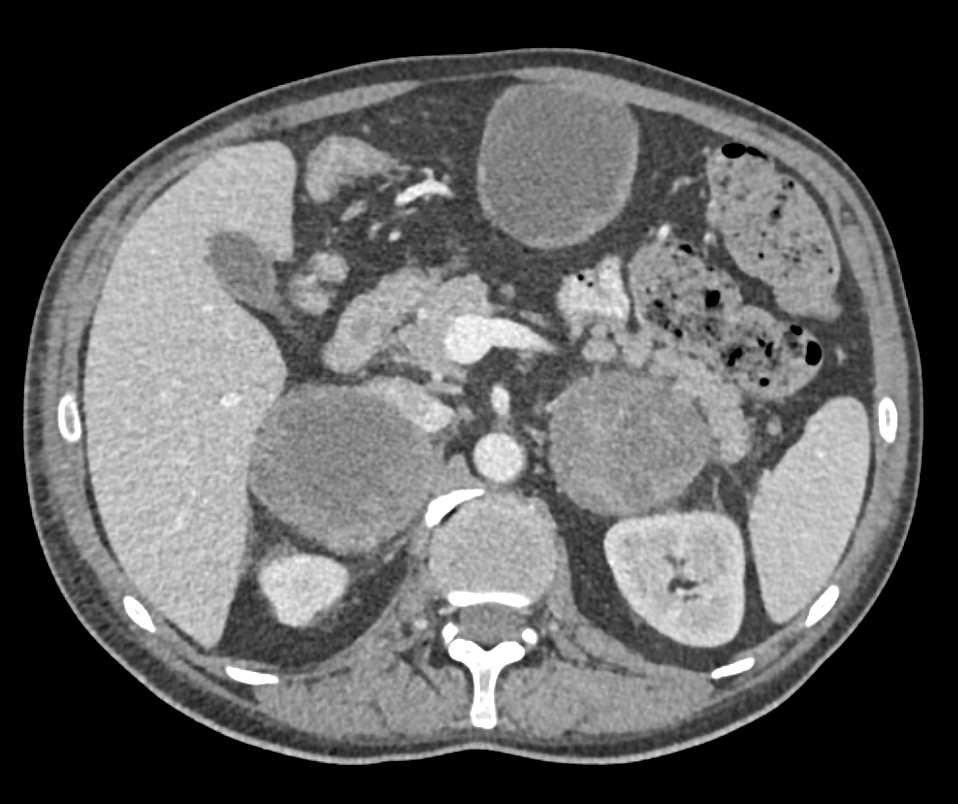

Melanoma Metastatic to Small Bowel and the Adrenal Glands